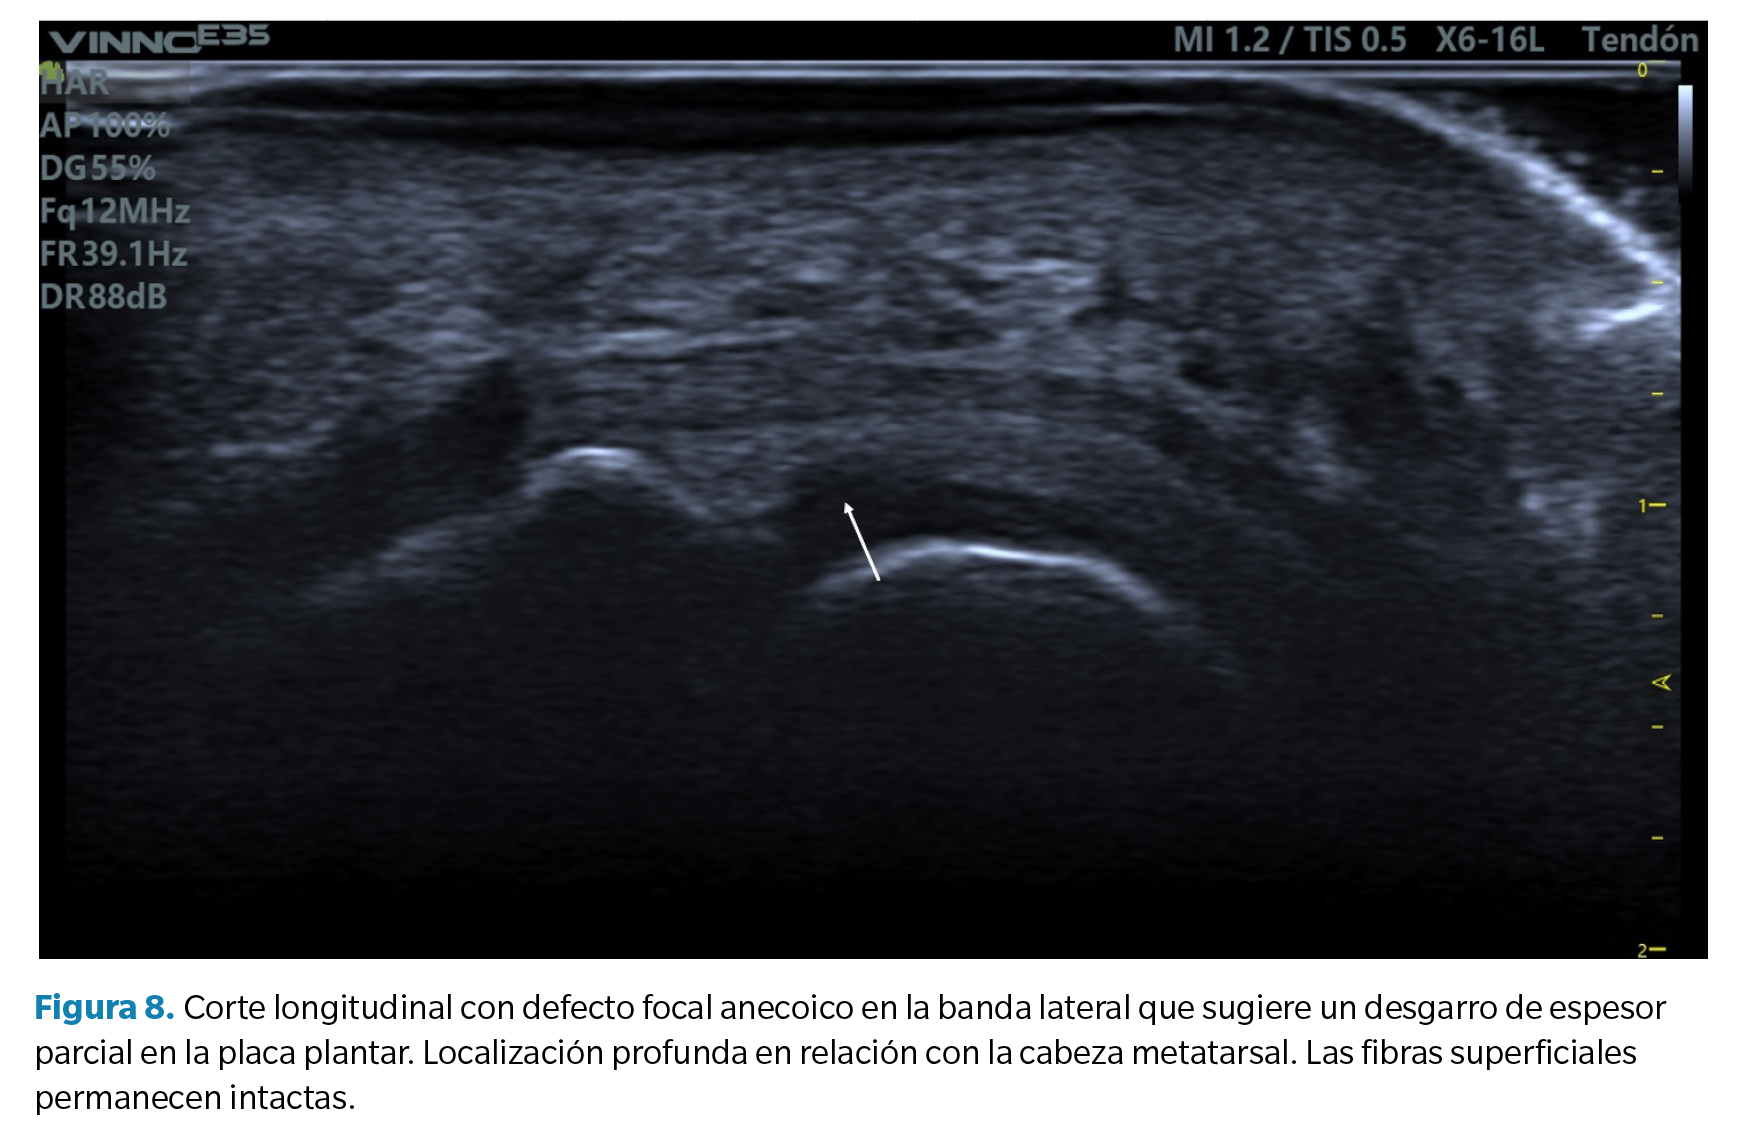

- Defecto focal anecoico o hipoecoico. Se aprecian como una hendidura discreta en la zona profunda del tejido (zona que articula con la cabeza metatarsal) en su margen lateral. Cuando las fibras superficiales están intactas hablamos de un desgarro de espesor parcial, mientras que cuando dicho desgarro atraviesa todo el tejido hasta su región superficial hablamos de un desgarro de espesor total39 (Figura 8).